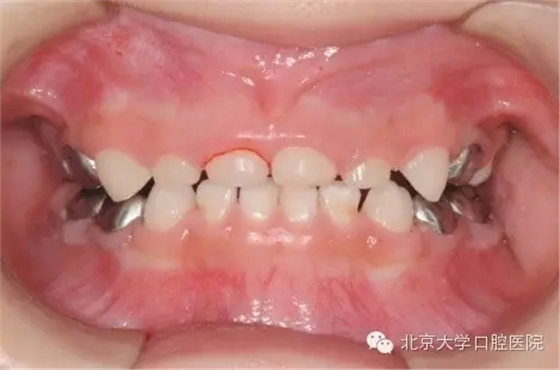

全麻治療因?qū)⒂?jì)劃進(jìn)行的所有治療集中在一次完成,而這些治療在常規(guī)門診時(shí)可能要十余次才能完成,因此牙齒治療的反應(yīng)有疊加,在全麻治療術(shù)后可能出現(xiàn)明顯的咬合不適,牙齒腫痛等情況,請(qǐng)遵醫(yī)囑進(jìn)行有針對(duì)性的處理,一般說來一段時(shí)間后這些癥狀都能消退。7為什么孩子的牙做了牙套?

全麻治療中醫(yī)生對(duì)缺損較大的后牙經(jīng)常會(huì)采用“預(yù)成冠”修復(fù)的方法,預(yù)成冠由不銹鋼制成,可以很好的恢復(fù)牙齒的外形并預(yù)防牙齒及充填體折斷,并不影響牙齒替換。